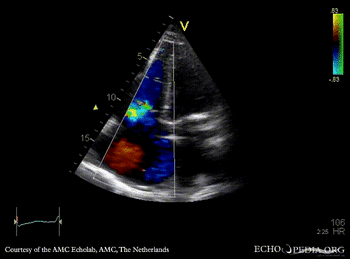

Subcostal view: severe tricuspid regurgitation